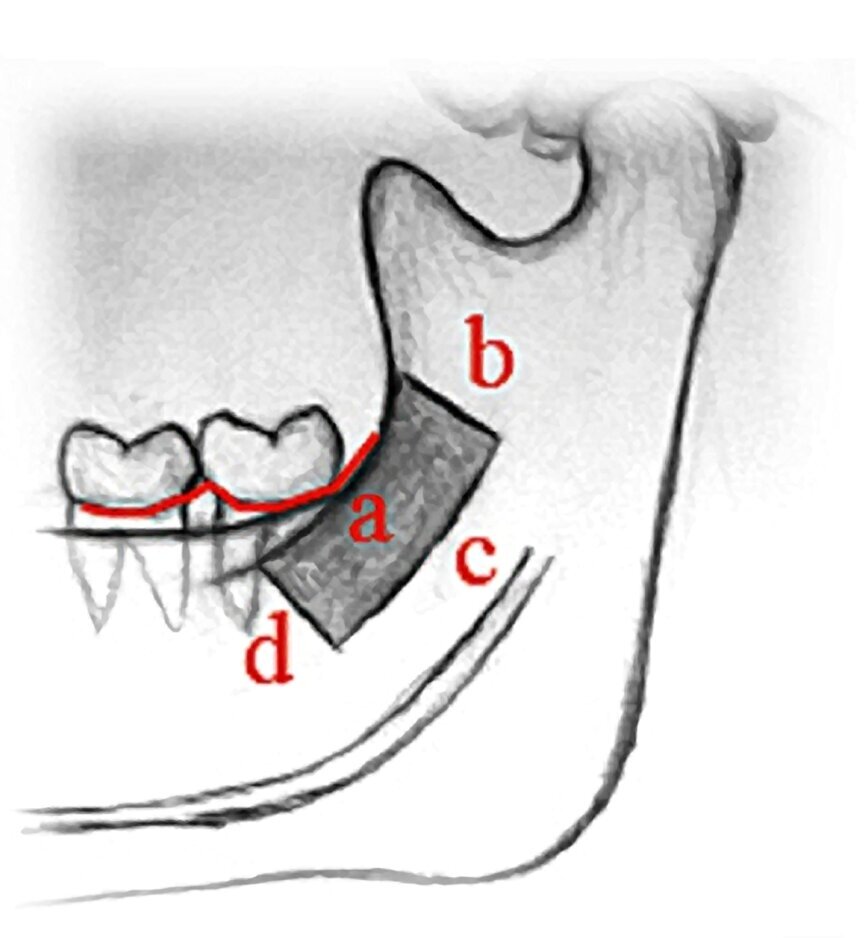

RAMA MANDIBULAR

- Anestesia troncular bilateral e infiltrativa

- Incisión medial a la cresta oblicua externa que se extiende lateralmente y anteriormente a la almohadilla retromolar, no se

extiende más allá del plano oclusal para no dañar la arteria e intrasurcular en molares

Aloinjerto1 - Elevación del colgajo a espesor total

- Osteotomías

• a. Corte oblicuo externo: parte anterior al proceso coronoides y 3-5 mm medial a la cresta oblicua. Puede extenderse hasta distal del 1º molar.

• Longitud del corte:

15 o 40 mm si es para uno o mas dientes respectivamente.

b. Corte superior de la rama: por encima y perpendicular a la cresta oblicua externa.

• c. Corte anterior del cuerpo mandibular: extensión hacia la región del 1º y 2º molar.

• d. Osteotomía inferior de grosor parcial

- Despegamiento del injerto con cincel a lo largo de la osteotomía oblicua externa paralela a la pared lateral de la rama para no dañar el nervio alveolar inferior

- Conservación del injerto en solución salina

- NO recolectar hueso esponjoso adicional

- Redondear cualquier borde afilado que quede en la rama con fresa o lima

- Reposición del colgajo

- Sutura 3/011